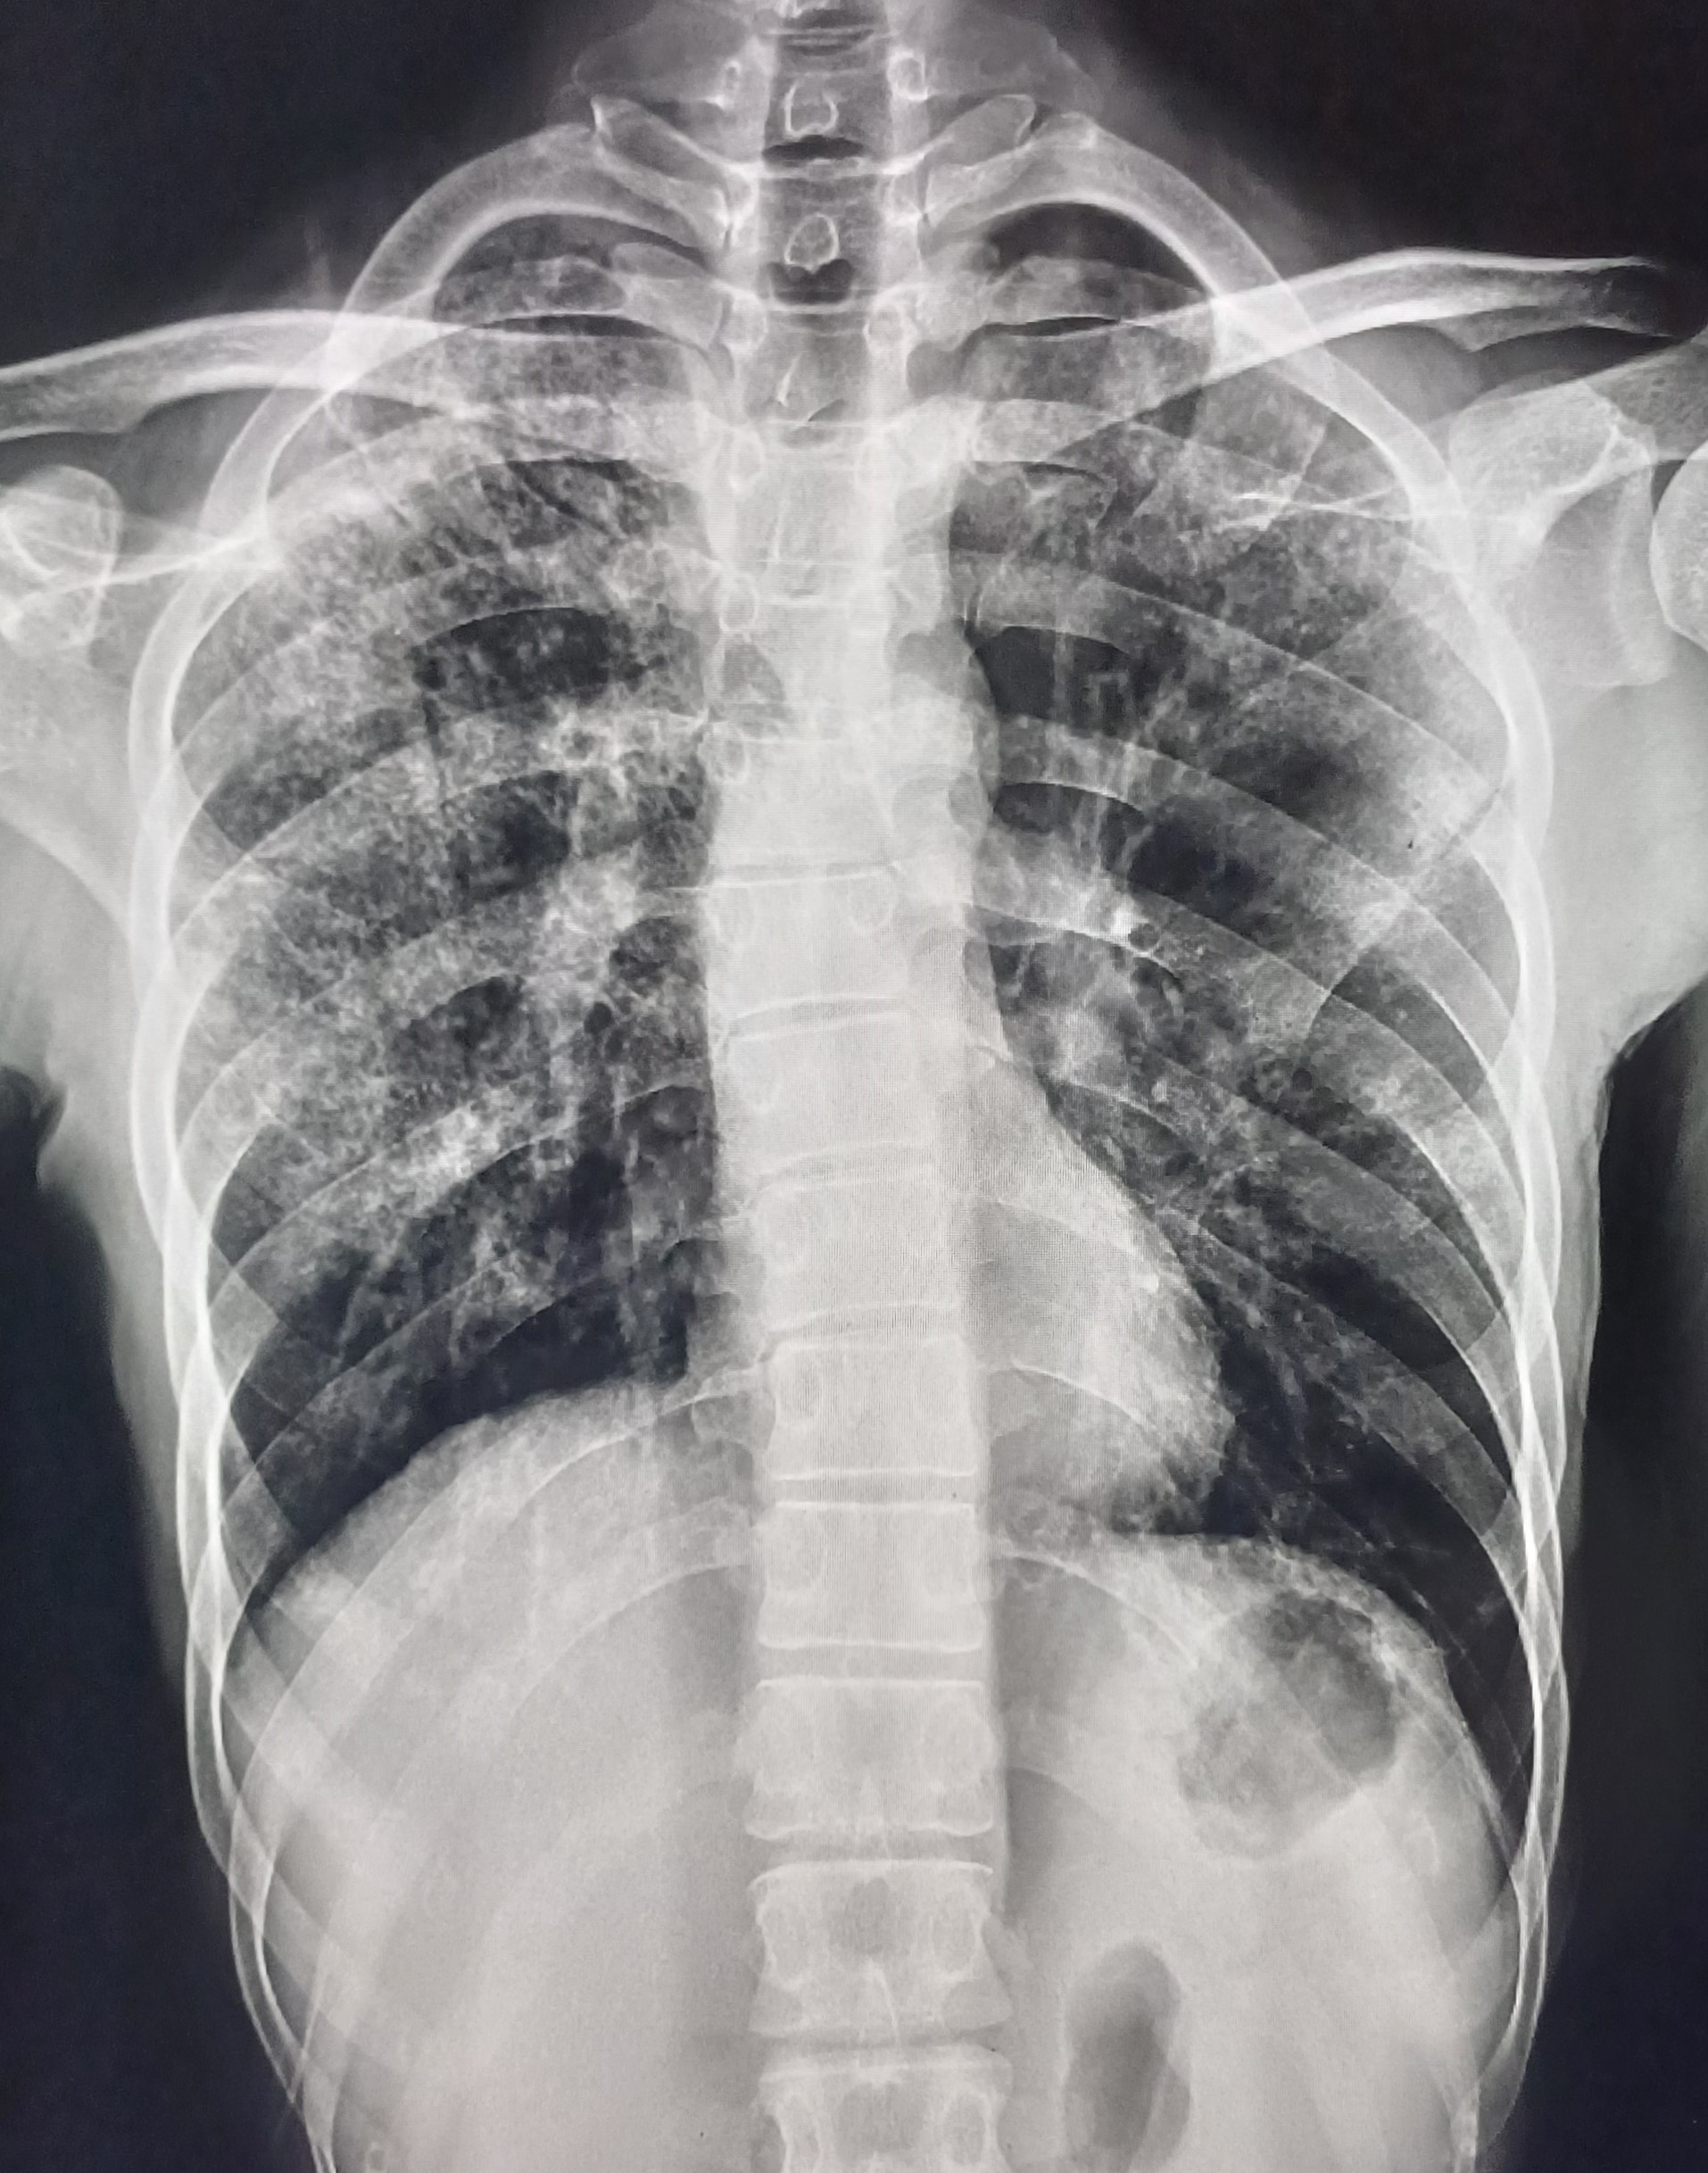

| 34 | IGGMC, Nagpur, Nagpur | P2 | 29-4438 | Palash Ambade | Consent taken on Paper | 34 Yrs. |

Provisional Diag : Pulmonary Tuberculosis

Final Diag : TB Infiltration |

TB Case (Confirmed) | Multiple Homogenous Nodular Opacities in Bilateral Lung fields Few Of Them Are Forming Consolidation | Abnormality visible on x-ray |

View |

|||